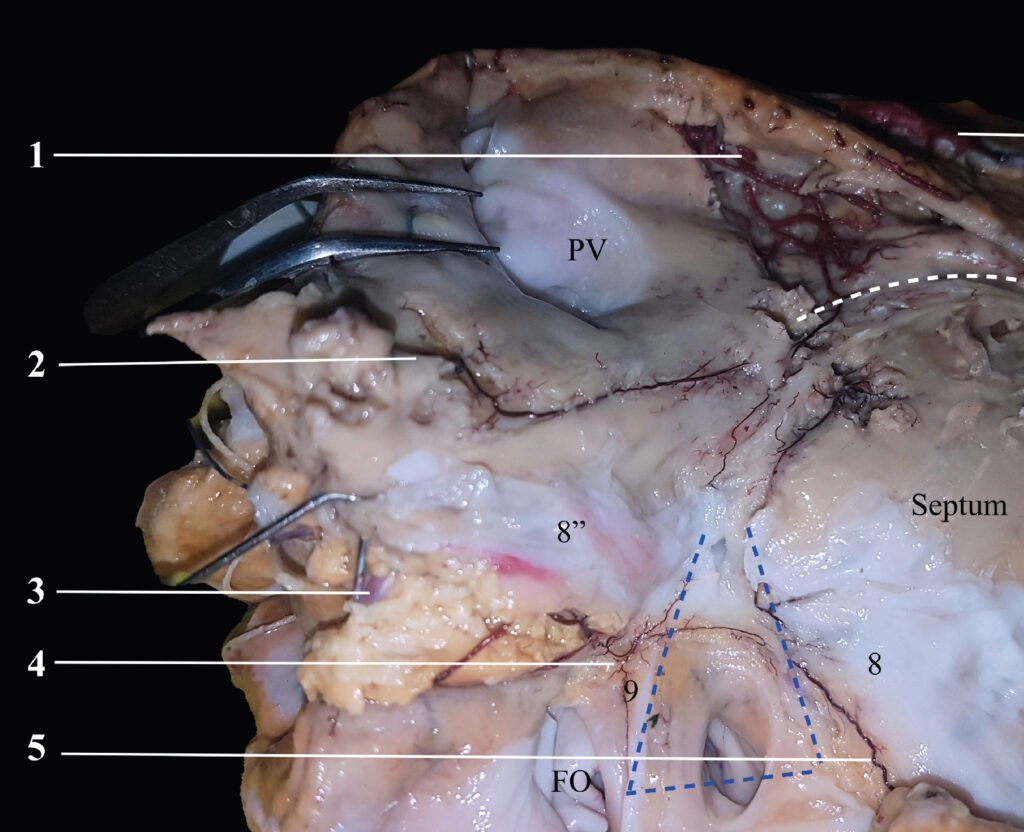

Museo.

Encontrarás los preparados de nuestro laboratorio en el museo de Anatomía J. J. Naón, Facultad de Medicina, Universidad de Buenos Aires, con su descripción.

Encontrarás los preparados de nuestro laboratorio en el museo de Anatomía J. J. Naón, Facultad de Medicina, Universidad de Buenos Aires, con su descripción.